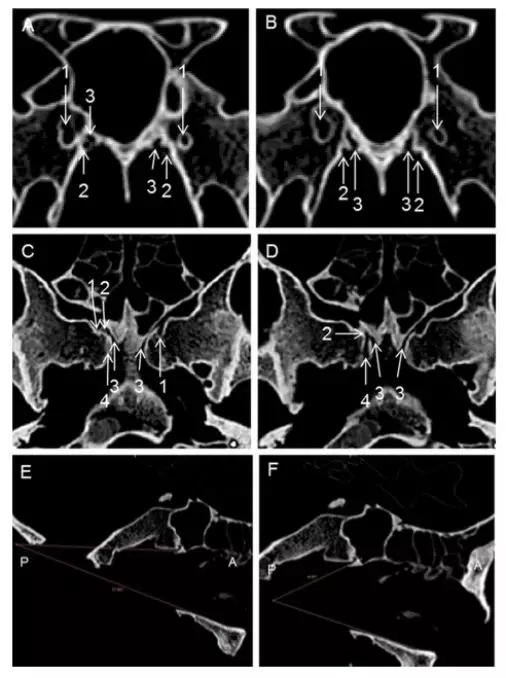

图示:1 翼管,2 腭鞘管,3 犁鞘管,4 后沟,5 蝶骨鞘突,6 犁骨,7 蝶窦开口。冠位CT的左侧2为插入探针后的腭鞘管。

图示:a、右侧腭鞘管前开口层面的轴位ct。右侧翼管与犁鞘管形成的夹角(黄线)大于翼管与腭鞘管的夹角(绿线)。腭鞘管前开口向前洞口样扩大,如果从此处往后寻找该管,很有可能会将犁鞘管误认为腭鞘管,有许多之前的文献都犯了这种错误。b、右侧腭鞘管后开口层面的轴位ct,刚好位于a图的下两个层面。可以同时看到右侧翼管、腭鞘管与犁鞘管。c、为b图的下两个层面。尽管此时左侧的后沟非典型的管样结构,但其锐利的外侧缘依然有助于定位腭鞘管。而右侧的后沟显示很清晰,平行于正中线。d、另一位患者的斜位重建显示了右侧腭鞘管全长、腭鞘管与犁鞘管间的骨性分隔、后沟。1 翼管,2 腭鞘管,3 犁鞘管,4 后沟。

图示:颅骨标本解剖及ct影像。a、右侧腭鞘管后开口层面的周围ct。右侧后沟呈一个近乎平行矢状面的管样结构。b、另一标本左侧腭鞘管后开口层面。左侧后沟往后洞口样扩大,其外侧缘锐利而清晰,大致平行矢状面。c、颅底的下面观,该标本的双侧后沟均为狭窄的沟状。d、另一例标本的下面观提示其左侧后沟呈椭圆形的窝状。e、内镜下观察左侧颅底标本,腭骨蝶突已被部分磨除,后沟与犁鞘管之间的骨性分隔清晰可见。f、完全去除腭骨蝶突,显示翼腭窝内的犁鞘管与腭鞘管。1 翼管,2 腭鞘管,3 犁鞘管,4 后沟,5 腭骨蝶突。

图示:一例已移除探针的颅骨标本的ct影像。a、腭鞘管前开口层面的冠状位重建。犁鞘管位于腭鞘管上内侧,而翼管位于此两者上方。腭鞘管前份与犁鞘管间的骨性分隔很菲薄。b、腭鞘管后开口层面的冠状位重建。这个层面时腭鞘管与犁鞘管间的骨隔相当厚。犁鞘管往上走形至蝶窦底壁。c、腭鞘管前开口层面的轴位ct。后沟的上壁可以辨认,但不足以用来定位腭鞘管。犁鞘管与腭鞘管呈斜行关系增加了区别两管的难度。可以清楚地看到左侧犁鞘管的全长,但常被误认为腭鞘管。d、腭鞘管后开口层面的的轴位ct,为c图的下两个层面。后沟近乎平行中线、呈长管状,顺其往前上方,很容易辨认出腭鞘管。e、矢状位重建。后沟与硬腭的平均夹角为17.9度,提示在平行硬腭扫描的轴位层面上更容易辨认出后沟。f、腭鞘管与硬腭平均夹角为44.85度,提示在平行硬腭扫描的轴位层面上不好辨认腭鞘管。1 翼管,2 腭鞘管,3 犁鞘管,4 后沟。